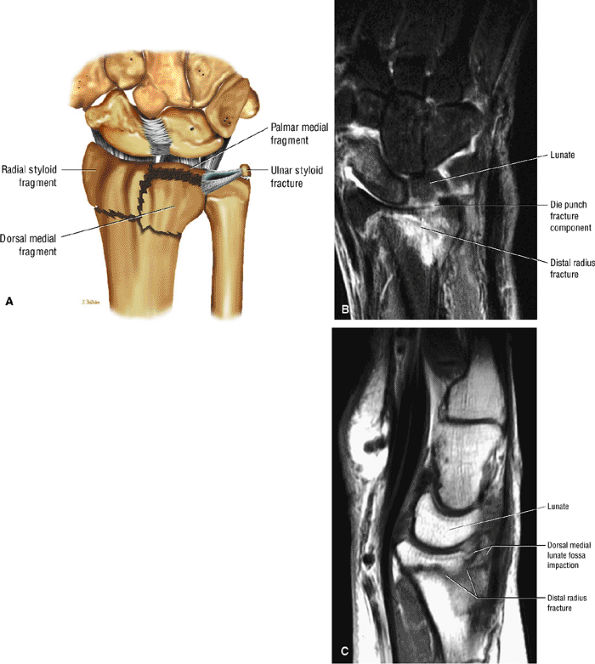

At the site of the radiolunate articulation, the distal articular surfaces of the radius and ulna are usually at the same level (i.e., neutral ulnar variance). Alternatively, the ulna may be relatively long (positive ulnar variance), leading to an ulnar abutment syndrome, or relatively short (negative ulnar variance), as is often seen in Kienböck's disease. The distal radius forms two facets that articulate with the scaphoid and lunate of the proximal carpal row. This articulation of the proximal pole of the scaphoid in the scaphoid fossa is quite congruent, and even a small degree of malrotation of the scaphoid may cause incongruent loading of the articular cartilage and subsequent degeneration (such as that which accompanies a SLAC wrist, as described by Watson and Ryu37). The lunate facet commonly becomes incongruent following distal radius fractures, especially die-punch-type fractures. The interosseous ligaments join the proximal carpal bones at their proximal edges.36